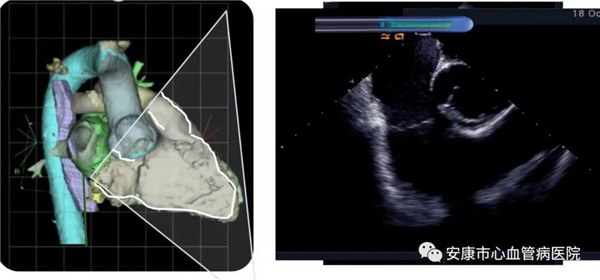

心律失常團(tuán)隊(duì)在11月6日為患者在ICE引導(dǎo)下行房撲射頻消融術(shù)。穿刺左鎖骨下靜脈,導(dǎo)絲走行證實(shí)了合并永存左上腔靜脈。穿刺右股靜脈,分別送入心腔內(nèi)超聲導(dǎo)管和消融電極,超聲下建立右心室、右心房、左心室、左心房、二尖瓣和三尖瓣及三尖瓣峽部模型。ICE就像術(shù)者多了一雙天眼,可以對(duì)心臟內(nèi)部結(jié)構(gòu)一目了然,360度無(wú)死角觀察心臟結(jié)構(gòu),可以做到“所視即所及”。建模后,消融三尖部峽部,房撲很快終止,轉(zhuǎn)為竇性心律,手術(shù)獲得成功!手術(shù)用時(shí)僅70分鐘,術(shù)后病情穩(wěn)定,安全返回病房。

心腔內(nèi)超聲(Intracardiac Echocaiography ICE)是將微型的換能器安裝在心導(dǎo)管的尖端,再經(jīng)外周血管(動(dòng)脈或靜脈)送至心腔,換能器發(fā)射聲波,然后將接受到的回波經(jīng)計(jì)算機(jī)處理后形成超聲圖像。由于換能器放置在心腔內(nèi),不受空氣等因素的干擾,因此比經(jīng)食道超聲檢查圖像更加清晰,可以辨別心內(nèi)的細(xì)微結(jié)構(gòu),臨床上主要用于指導(dǎo)心律失常的射頻消融治療。

ICE不僅能檢查左心耳結(jié)構(gòu)、指導(dǎo)房間隔穿刺,而且能精確構(gòu)建左房及肺靜脈解剖結(jié)構(gòu),量化前庭部位與肺靜脈口部的距離,精準(zhǔn)的消融一些復(fù)雜心律失常病例;并且能精確構(gòu)建食道,量化食道與后壁的距離,降低食道損傷幾率;術(shù)中動(dòng)態(tài)監(jiān)測(cè)積液變化,實(shí)時(shí)監(jiān)測(cè)并發(fā)癥,早發(fā)現(xiàn)早處理。因此心腔內(nèi)超聲真可謂是房顫射頻消融手術(shù)安全保障的一只“天眼”。此外這只“天眼”現(xiàn)在還應(yīng)用于心臟瓣膜手術(shù)、起搏器植入等心臟介入手術(shù)。